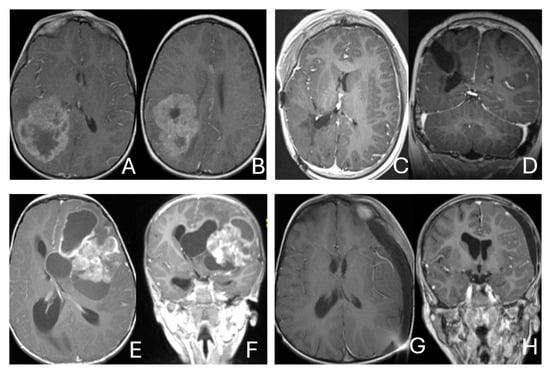

Objectives: Atypical teratoid/rhabdoid tumors (ATRTs) are rare, malignant central nervous system (CNS) neoplasms that predominantly affect infants and young children. While ATRT arises throughout the CNS, its extracranial counterpart, malignant rhabdoid tumor, occurs in other organs. A single-institutional cohort is reviewed to map anatomic distribution of pediatric ATRTs and to integrate a literature review to contextualize ATRT histogenesis from anatomical and embryological perspectives. Methods: A retrospective review was conducted on a cohort of 50 pediatric patients with ATRT treated over 20 years. Demographic, surgical, and neuroimaging data were correlated to define tumor location, extent, and compartmental involvement. A focused literature review synthesized molecular subclassifications and proposed cells of origin/cytogenesis. Results: Of the 50 ATRTs, 18 (36%) were infratentorial, 15 (30%) supratentorial, 11 (22%) in the pineal region, and 6 (12%) in the spinal compartment. Among infratentorial tumors, 10 were centered in the fourth ventricle, with or without extension into the cerebellopontine angle (CPA) cistern; the remainder arose in the CPA. Among ATRTs of the cerebral hemispheres, 3 showed bi-hemispheric involvement crossing the falx cerebri. ATRTs of the pineal region predominantly originated from the superior medullary velum. These topographic data were corelated with embryological and molecular information available in the literature. Conclusions: ATRTs arise across diverse neuroanatomical compartments—including intraparenchymal, intraventricular, extra-axial, and extradural sites—underscoring biological heterogeneity. Inactivation of SMARCB1 is the defining molecular event and principal oncogenic driver, although the upstream mechanisms precipitating these alterations remain incompletely resolved. Molecular subgroups—ATRT-TYR, ATRT-SHH, and ATRT-MYC—display distinct age distributions and anatomic predilections, implicating developmental context in tumor initiation. The characteristic cellular admixture of rhabdoid cells with mesenchymal and/or epithelial differentiation, together with intra- and extra-axial and occasional extradural presentations, supports a model in which at least a subset of ATRTs may originate from neural crest-derived lineages, despite little or no neural crest contribution to brain parenchyma development. Neural plate border progenitors with bipotent features represent a plausible intraparenchymal cell of origin. Definitive resolution of these origins and the mechanisms of SMARCB1 disruption will require integrated approaches. Further investigations are warranted to clarify these mechanisms.